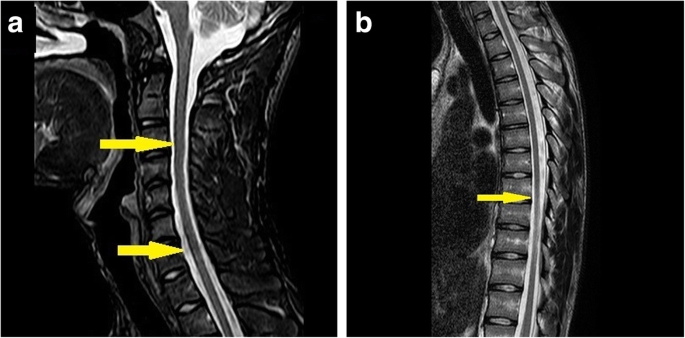

Brain MRI revealed a high-intensity signal in the left central gyrus cortex by fluid-attenuated inversion recovery (FLAIR) as well as T2-weighted images, while a decreased signal in the T1-weighted images and high-intensity lesions in the bilateral corticospinal tracts were detected (Fig. 3). Cervical spine and thoracic spine MRI showed mild atrophy of the spinal cord (Fig. 4). Moreover, electromyography indicated peripheral nerve demyelination, and both visual evoked potentials (VEP) and brainstem auditory evoked potential (BAEP) were normal.

In the Patient 1, electromyography indicated peripheral nerve demyelination, while brain MRI showed an increased signal intensity in the white matter encompassing the bilateral corticospinal tracts. The GALC enzymatic activity in leukocytes was 3.9 nmol/mg/17 h. In the Patient 2, the GALC enzymatic activity revealed 4.4 nmol/mg/17 h. These low activities proposed the diagnosis of Krabbe disease in both patients.